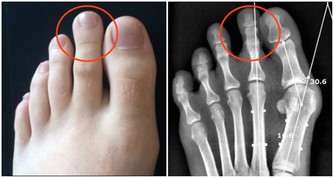

***1.牙周炎,齲齒,口腔護理沒做好***

有很多人一天只有刷一次牙的習慣,除了早上刷牙,晚上吃了宵夜都不刷牙的,這樣的口腔清潔不到位,很容易造成牙齒的多種問題,例如牙周炎、齲齒、牙菌斑等等,久而久之牙齒裡面的殘渣剩菜得不到有效的清理,很容易腐爛變臭。